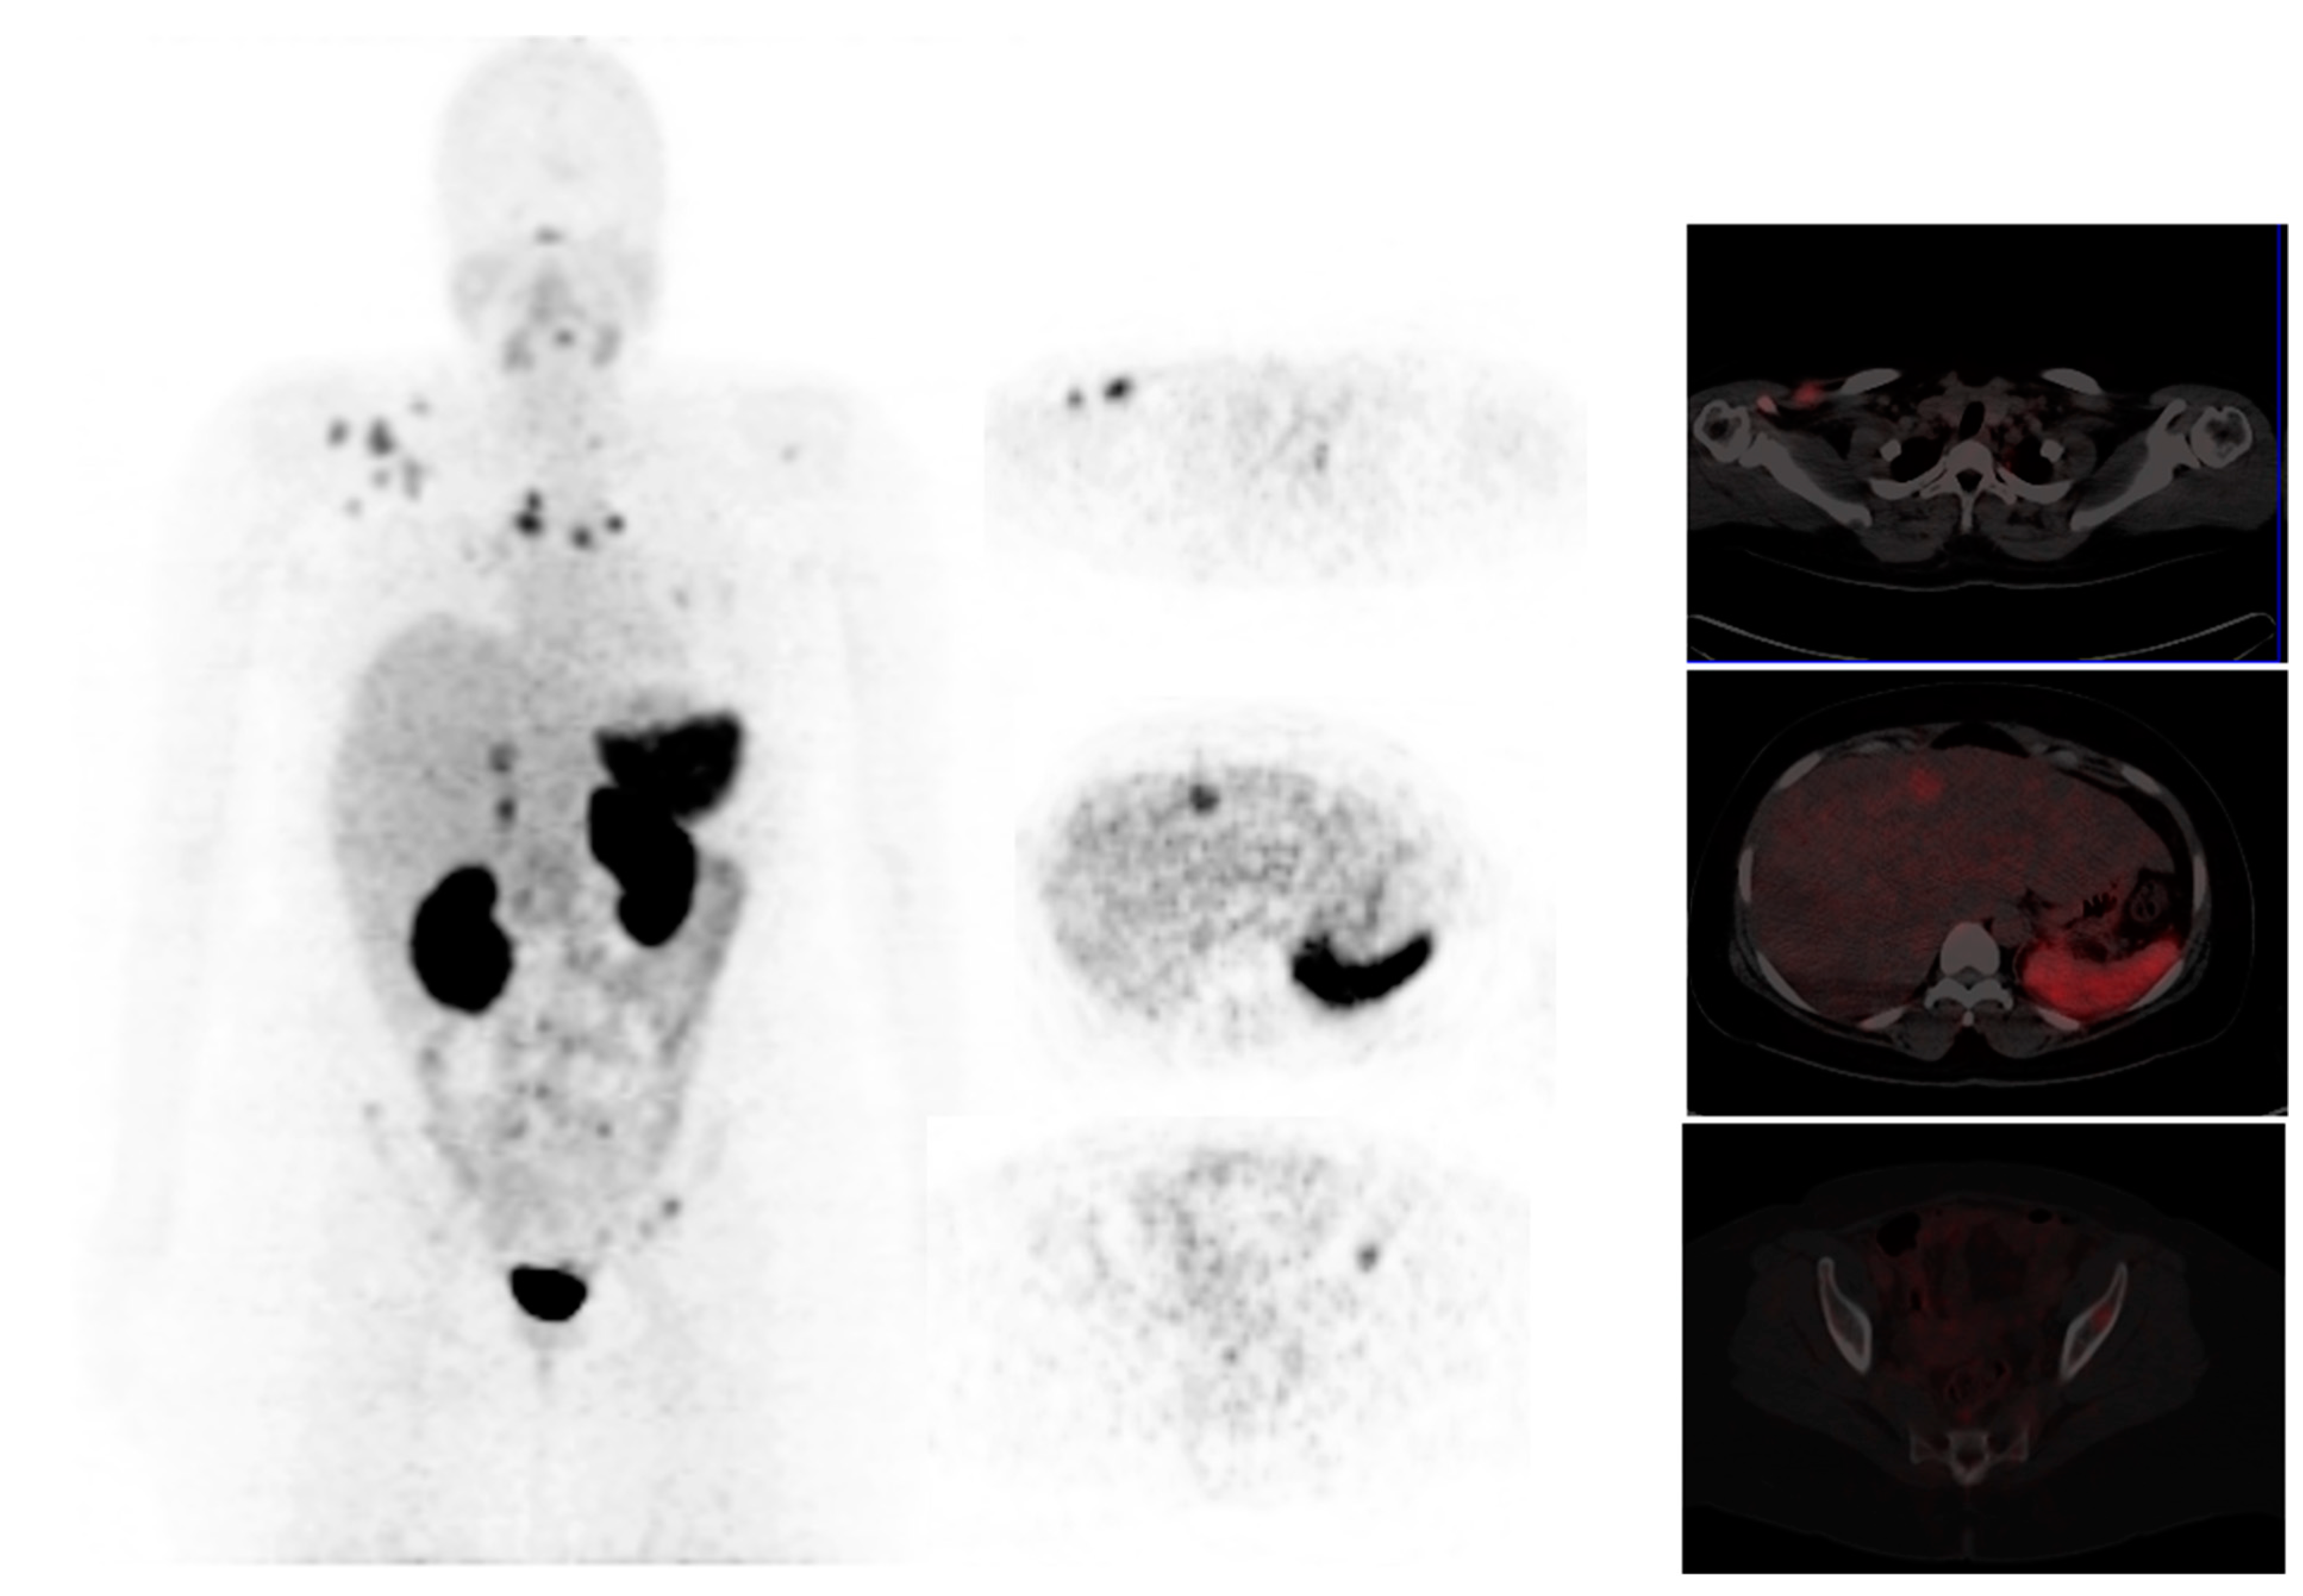

3.13.1. 18F-NaF Bone Imaging

3.13.2. 68Ga- Zoledronate